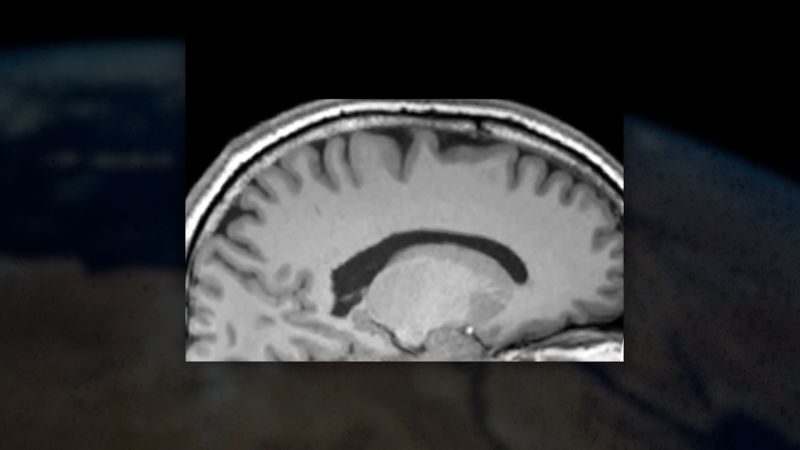

Що відбувається з тілом? Космічна мікрогравітація спричиняє незвичний перерозподіл рідин в організмі. Відсутність гравітаційного тиску змушує рідини переміщатися вгору й накопичуватися в верхній частині тіла, зокрема, в голові. Це може викликати набряки обличчя, закладеність носа та навіть погіршення зору. Синдром, що виникає через цей процес, отримав назву Космічний нейро-окулярний синдром (SANS), і він стає серйозною проблемою для астронавтів.

Мозок також зазнає змін. Космічні мандрівки супроводжуються когнітивними змінами: зниженням уваги, проблемами з пам'яттю та уповільненням реакцій. Стрес від ізоляції, недостатньої кількості сну та фізичні навантаження у міко-гравітації залишають свій відбиток.